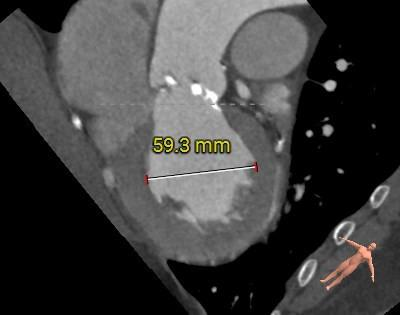

3.左心室舒张期前后径59mm,术中发生恶性心律失常风险大,预装瓣膜,备自动除颤仪和体外循环。

冠脉阻挡风险及左室大小评估